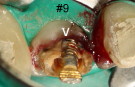

Remove #9,10 crowns, #9 lingual margin subgingival; pulpal test: #8,10 necrosis. Remove #9 post, redo RCT, #8, 10 RCT, #8,10 in office internal bleaching; #9 cast post, ortho extrusion before #9,10 crowns

#18 mesiolingual tilt, #19 traditional implant and extract #17; once #19 implant is osteointegrated, it is to be used as an anchorage to upright #18, elastics between #15 buccal hook and 18 lingual button to correct linguoversion of #18